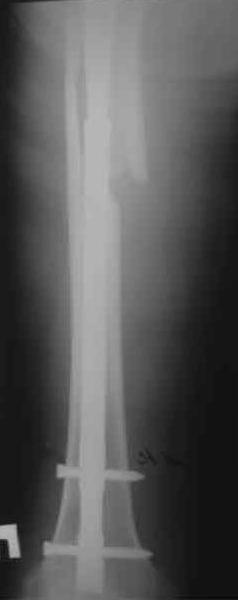

Произведено закрытое удлинение ножки эндопротеза с помощью ретроградного интрамедуллярного стержня. Продолжительность операции 3 часа. Два из них закрытое восстановление длины бедра диистрактором

таз-бедро.